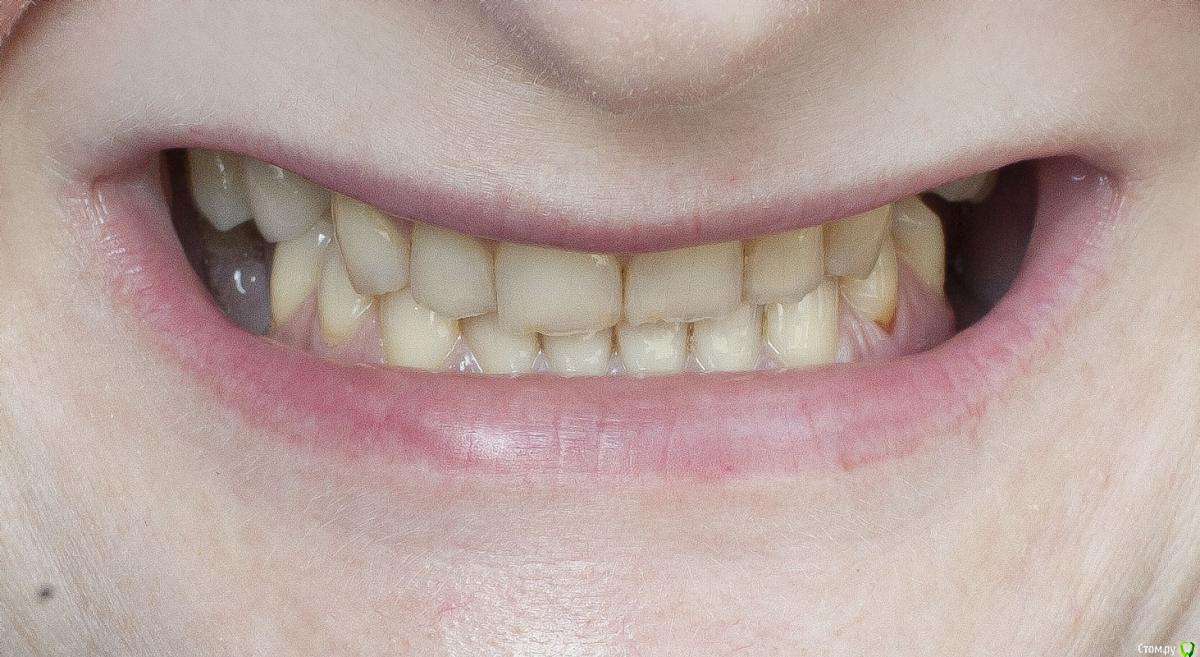

Barbar Опубликовано 16 июля, 2015 Поделиться Опубликовано 16 июля, 2015 Добрый день! У меня неправильный прикус и отсутствуют зубы 14, 24, 25, 36, 37, 46, которые я в ближайшее время собираюсь заменить имплантами. Мне 43 года.Подскажите, пожалуйста, с чего начать: с имлантов или исправления прикуса? Возможно ли решить проблему прикуса брикетными системами? можно ли исправить лингвальными брикетами? применить на обе челюсти?Или есть другое решение?Огромное спасибо за рекомендации заранее! Ссылка на комментарий

Barbar Опубликовано 16 июля, 2015 Автор Поделиться Опубликовано 16 июля, 2015 Дополнительные фото: Ссылка на комментарий

Barbar Опубликовано 21 июля, 2015 Автор Поделиться Опубликовано 21 июля, 2015 что именно Вам мешает широко улыбаться??? форма зубов, их расположение, отсутствие боковых зубов...? что именно Вы хотели справить с помощью брекетов? Вам стоматолог посоветовал заниматься прикусом или это Ваши предположения? если хотите просто поставить отсутствующие зубы - то Вам к ортопеду надо. Он посмотрит и скажет , ДОСТАТОЧНО ли места по ширине и высоте для имплантации и протезирования. если да, то просто протезируйтесь. Если же нет - то тогда Вам к ОРТОДОНТУ. Да, да и да! " форма зубов, их расположение, отсутствие боковых зубов..."Ладно, их расположение устраивает, во рту они как раз на правильном месте %РМне не нравится, что зубы пожелтели, неровны и сточены, особенно нижние. И прикус!Верхние зубы направлены немного вовнутрь и перекрывают нижние, у которых от этого сильный наклон вовнутрь. Уж не знаю как лучше объяснить, я не врач и терминами не владею. Думала, что всё понятно по фото. Улыбка получается жалкая. Имплантаты на место отсутствующих зубов будут ставить, уже решено. 6 штук, что недёшево. Но хотелось наконец решить эту проблему так, чтобы не было мучительно... то есть все продумать и закрыть тему зубов на долгие годы. Исправить прикус тоже.Мои вопросы были - с чего начать? Какие варианты? Помогут ли (для прикуса) просто коронки на передние нижние зубы? тогда придётся закрыть коронками весь ряд? или только 6 зубов? Или поставить имплантаты и постепенно исправлять прикус лигвальными брикетами? Но тогда высота имплантатов после исправления будет недостаточной? Ссылка на комментарий

Barbar Опубликовано 23 июля, 2015 Автор Поделиться Опубликовано 23 июля, 2015 И причём безо всяких брикетов. По сценарию: пришла, заснула, очнулась - мне зубы, а ему деньги. Я думаю, это мечта любого стоматолога (прошу не обижаться, это добрая шутка)По поводу эстетики - вам правда мои зубы кажутся в полном порядке или просто у вас мои фото в полный размер не открываются? На последней фотографии особенно видно, что нижние зубы сточены и пожелтели, а верхние неровные, имеют зазубренные края и частично уже прозрачные, или нет? Вы, как стоматолог, можете видеть проблемы в зубах, кажущихся идеальными, что простым смертным не под силу, и при этом мои зубы Вам кажутся вполне эстетичными? Ссылка на комментарий